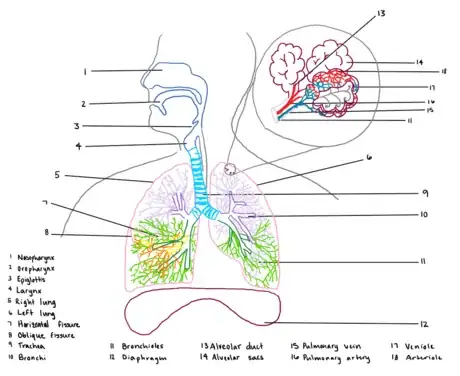

This guide will provide a description and example of how to draw the human respiratory system. First by outlining the lungs, bronchi, and trachea, then detailing additional components and accessory structures. By the end of this wikiHow, you will be proficient in drawing a medically accurate human respiratory system and be ready to ace your exams!

1Select a dynamic color scheme. For this activity, you will need 1-2 low contrast colors and 9 highlighting colors. There are several medical illustration standards to keep in mind, such as using blue for oxygenated blood flow and red for deoxygenated blood flow. Beyond those standards, it’s up to you how detailed you need your illustration to be.

3Draw the frame for the diagram. Outline the thoracic cavity, neck, and head. You will want this to be large enough for you to draw more detailed structures inside. For a small diagram, outline the thoracic cavity to be no smaller than 3 in (8 cm) wide to ensure clarity. Do this with a low contrast color, so you can use more vibrant colors to highlight structures.

4Illustrate the lungs. Draw two rounded, somewhat triangular shapes in the thoracic cavity with the base on the nipple-line and the apex at the clavicle. These are the lungs! These triangles should be angled upward at the base in the medial direction. This distinction is important because the diaphragm is located below the lungs and occupies this space.

- Additionally, a notch should be placed in the left lung which accommodates for the heart (part of the cardiovascular system, not included in this illustration).

5Outline the trachea and bronchi trunk. Using your lungs as a reference, draw an upside-down Y shape centered at the top quarter of the lungs and leading upward to the neck. The center point should be at the suprasternal notch, and the long part of the Y should extend to the Adam’s apple. This Y shape is the two bronchus trunks and the trachea. These structures are cylindrical with notches similar to what you would see on a tin of soup; adding this detailing is beneficial to your viewer because it allows them to better understand the physiology of the structure.

6Sketch the air passageways. Continue the sketch of the trachea to the rest of the neck up to the mouth. Now curve this structure through the mouth and to the lips. The section you’ve just drawn is the larynx leading into the oropharynx. The nasal passageway, or nasopharynx, begins at the nostrils and connects to the oropharynx at the mandibular angle.

1Include landmark structures. Parallel to the larynx and oropharynx is the esophagus (part of the digestive system) but should be included in your illustration as a low-contrast color. At the mandibular angle, a small “flap” should be noted; this is the epiglottis, which covers the trachea when swallowing to prevent debris from entering the lungs.

2Sketch the diaphragm. Draw a flat kidney bean shape following the outline of the base of the lungs. The diaphragm is a muscle that contracts during inhalation and relaxes during exhalation to modify pressure in the lungs.

3Detail the lobes of the lungs. Segment the right lung into 3 curved sections (draw the oblique and horizontal fissures) and the left lung into 2 curved sections (draw the oblique fissure) as distributed below; these segments are called lobes.

4Outline the branching. Extend the branching of the bronchus in each lung into a secondary bronchus in each lobe. Then extend this secondary branching with smaller bronchioles. It is helpful to do each lobe branch in a new color to distinguish the branching pattern.

5Draw a microscope bubble. Attached to these bronchioles are alveoli, which appear as small grapes. Detail several of these and then extend a microscope box away from your diagram to illustrate this structure more clearly.

6Detail the alveoli. Redraw a segment of the bronchioles and attached alveoli in the microscope box. The bulbous “grape” like structures of the alveoli are called alveolar sacs, and the segment of branching immediately before the alveoli are called alveolar ducts.

- In addition to these structures, draw an overlay of the pulmonary artery (red) and pulmonary vein (blue) leading into the arteriole and venule capillary system.

7Label your completed diagram. Draw lines away from each structure to an open space using a ruler or straight edge. Clearly label each structure or region correctly. For more complex drawings, it is sometimes beneficial to label structures numerically and then provide an organized key.

QuestionWhat is number 14 in the bronchioles?

GB742Top AnswererIn the case of this diagram, 14 indicates the alveolar sacs - this is the part of the lung where gas exchange occurs.

GB742Top AnswererIn the case of this diagram, 14 indicates the alveolar sacs - this is the part of the lung where gas exchange occurs.

To draw the human respiratory system, you'll need to outline the organs that make up the different parts and then add details to show how they function. Start by drawing an outline of the head, neck, and shoulders. Draw 2 rounded, somewhat triangular shapes in the cavity to represent the lungs and then add an upside-down Y shape for the trachea and the bronchi connected to the lungs. Then, sketch out the mouth and sinus passageways, and add the diaphragm beneath the lungs. From there, add lobes and branching to give the lungs more detail. You could also draw a microscope bubble and draw alveoli inside of it to illustrate the smaller structures inside of the lungs. Once you’ve finished your diagram, label all of the parts of the system. For tips about how to add an organized key to your diagram, read on!